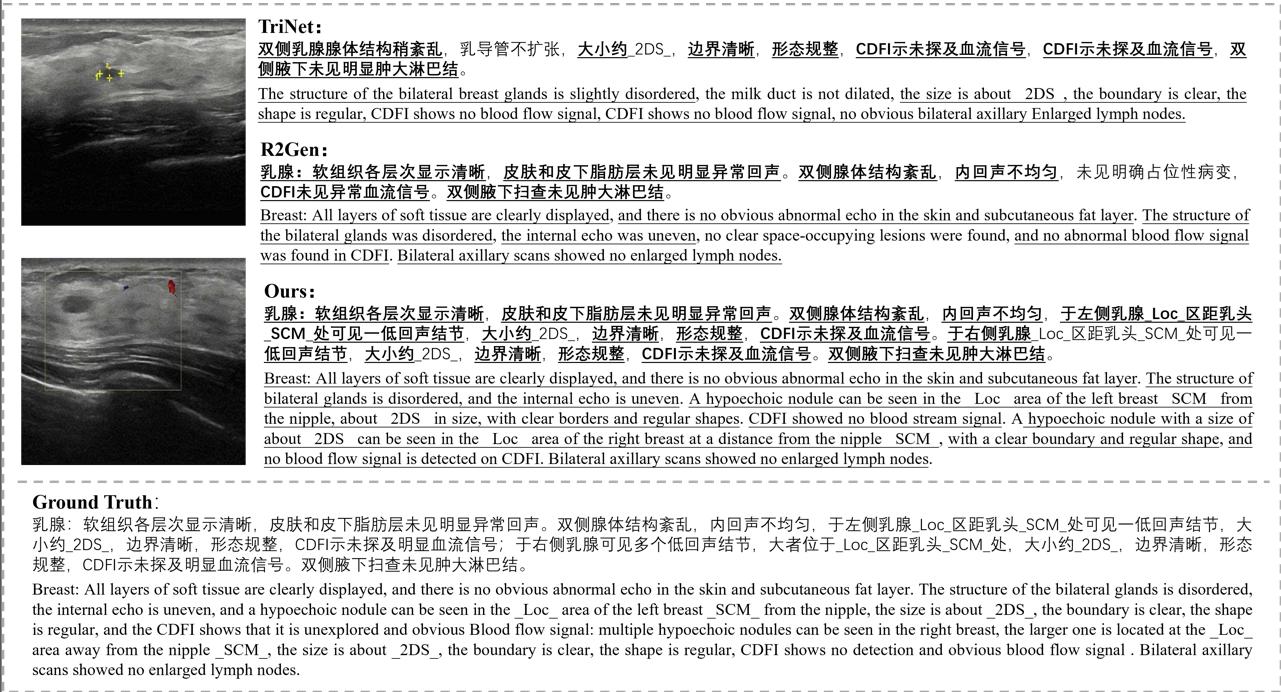

Jun Li, Che Liu, Wenjia Bai, Rossella Arcucci, Cosmin I. Bercea, Julia A. Schnabel.

[paper]

[project]

[huggingface]